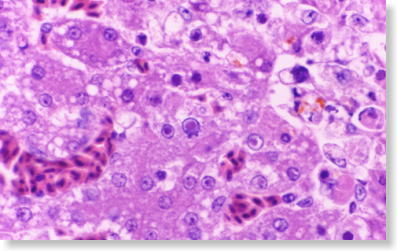

アデノウィルス感染症の肝臓組織

06 アデノウィルス感染症の肝臓組織